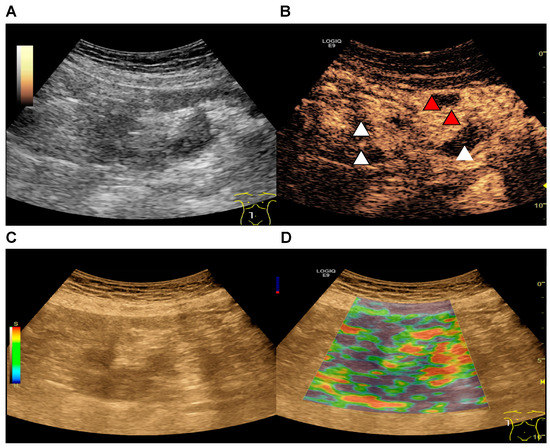

2.3. Strain Elastography

2.4. CEUS

2.5. Parametric Analysis